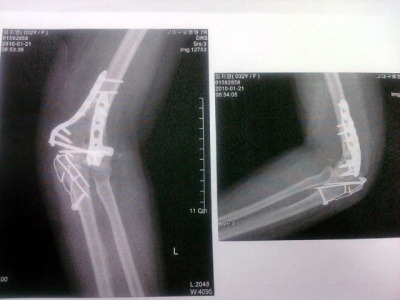

1/1일 넘어지면서 팔꿈치 8~10조각나서 분쇄 골절로 수술을 하였습니다.

대학병원에 재 입원 후 1/6일날 7시간의 대 수술을 하였습니다.

엑스레이나... CT상으로는 구부려 지지 않는 어떤 이유(?)가 발견되지 않는다고 하시면서 내복약 종류를 바꾸고 물리치료 꾸준히 받고.. 다시 2주 후에 뵙자고 하시네요..